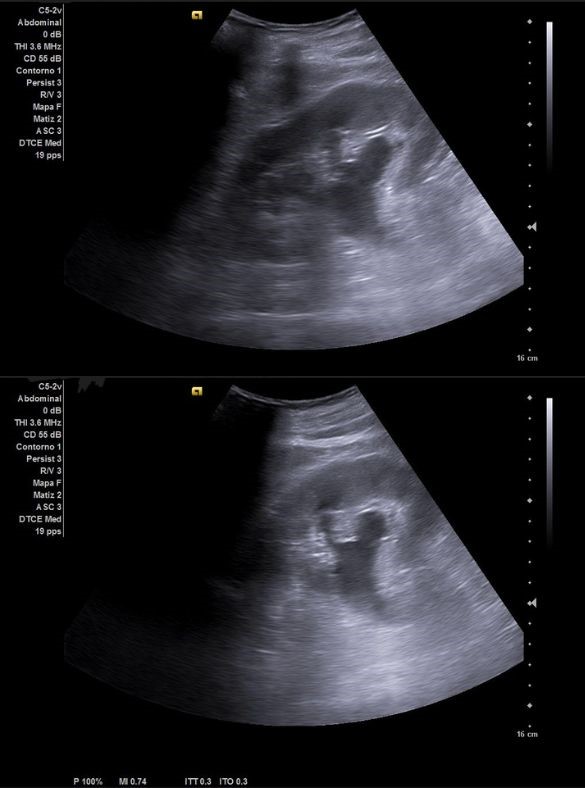

Ecografía clínica urológica: se objetiva vejiga muy distendida hasta epigastrio con imagen heterogénea en pared posterior de vejiga de gran tamaño que capta al Doppler color sospechosa de malignidad. Con signo de hidronefrosis riñón izquierdo grado III.